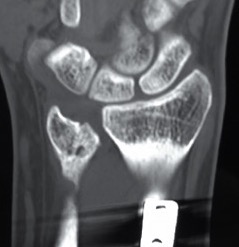

Xray

DRUJ instability

Post traumatic distal ulna osteoarthritis